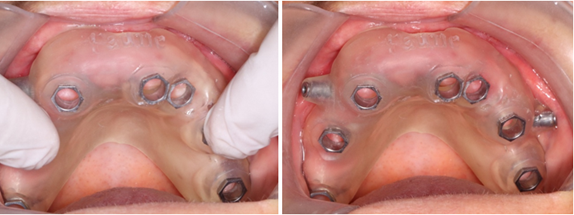

To make sure the printed guide fit precisely, a thorough evaluation was done before the surgery (Figure 20).

Figure 20: Adaptation of the guide in the mouth.

A local anesthetic was given, consisting of 2% lidocaine and 1:100k epinephrine. And fixation pins were drilled and inserted (Figure 21).

Figure 21: Insertion of fixation pins.

Then atraumatic excision of soft tissue at the surgical site by tissue punch on the 7 holes (Figure 22).

Figure 22: Tissue punch.

We follow the drilling protocol provided to place the implants with copious irrigation with saline solution and we finish by placement of the healing without sutures (Figure 23).

Figure 23: 7 healing screws placed.